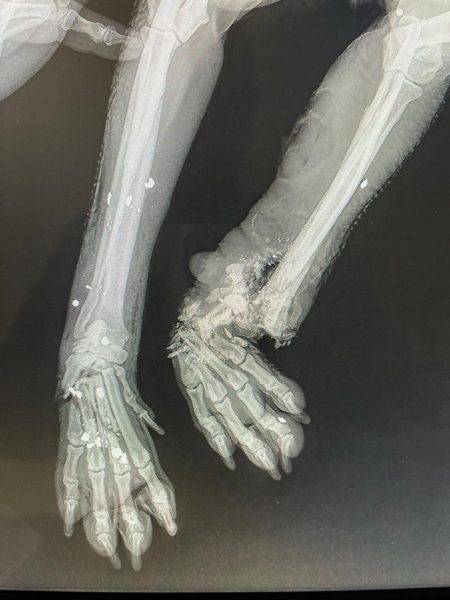

Οργή και αποτροπιασμό προκαλεί η άγρια κακοποίηση μιας μικροακαμωμένης σκυλίτσας στην Κρήτη. Από σπασμένα κόκκαλα μέχρι σφαίρα βρήκαν οι κτηνίατροι στο σωματάκι της, στο Αρκαλοχώρι Ηρακλείου. Με 3 πόδια πλέον το ζώο προσπαθεί να επανέλθει, την ώρα που οι δράστες παραμένουν άγνωστοι.

Σύμφωνα με το τοπικό Flashnews, η σκυλίτσα βρέθηκε σοβαρά χτυπημένη, με τα κόκκαλα στο ένα της πόδι κυριολεκτικά θρυμματισμένα, ενώ το οστό φαίνεται εκτεθειμένο. Παράλληλα, στο σώμα της βρέθηκαν σκάγια, τα οποία επιβεβαιώνουν πυροβολισμό!